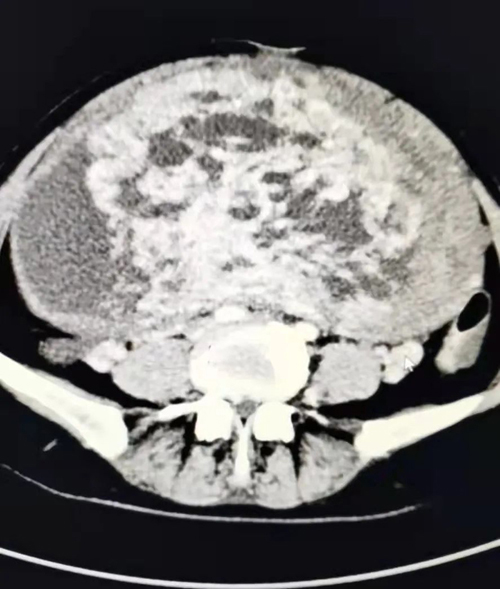

患者女,50歲,平素月經規律,無痛經,無異常陰道流血,近半月來出現無明顯誘因腹脹、輕度腹疼、小便頻,來我院消化內科就診,發現腹部異常膨隆,彩超見一巨大囊實性包塊,較大切面范圍約22.7*18.1CM,部分切面與宮底肌層關系密切,其內囊性部分呈多房樣改變,實性部分血流信號豐富,CA125 98.85U/ml,以“盆腔包塊瘤”收入婦二科。

3月1日下午15:30分,患者被推進手術室。按照術前制定的麻醉方案,麻醉醫師方軍為患者進行了橈動脈穿刺和中心靜脈置管,實時監測患者血壓變化,保證輸液通暢,確保患者手術中生命體征平穩。手術護士長安排了經驗豐富的護士甘瑾、邱靜靜和張兆霞配合手術。在麻醉科及手術室的支持配合下,手術有條不紊地進行。打開腹腔后,見子宮異常膨隆,占據整個腹腔、盆腔,緩慢吸引出囊腔內囊液約1500ml,將子宮搬出腹腔,沙袋壓迫上腹部,避免血壓驟降,手術歷經2個小時,完整切除了這一罕見的巨大肌瘤的子宮。術中快速病理為漿膜下平滑肌瘤,伴水腫囊性變。術后患者蘇醒,安返病房。